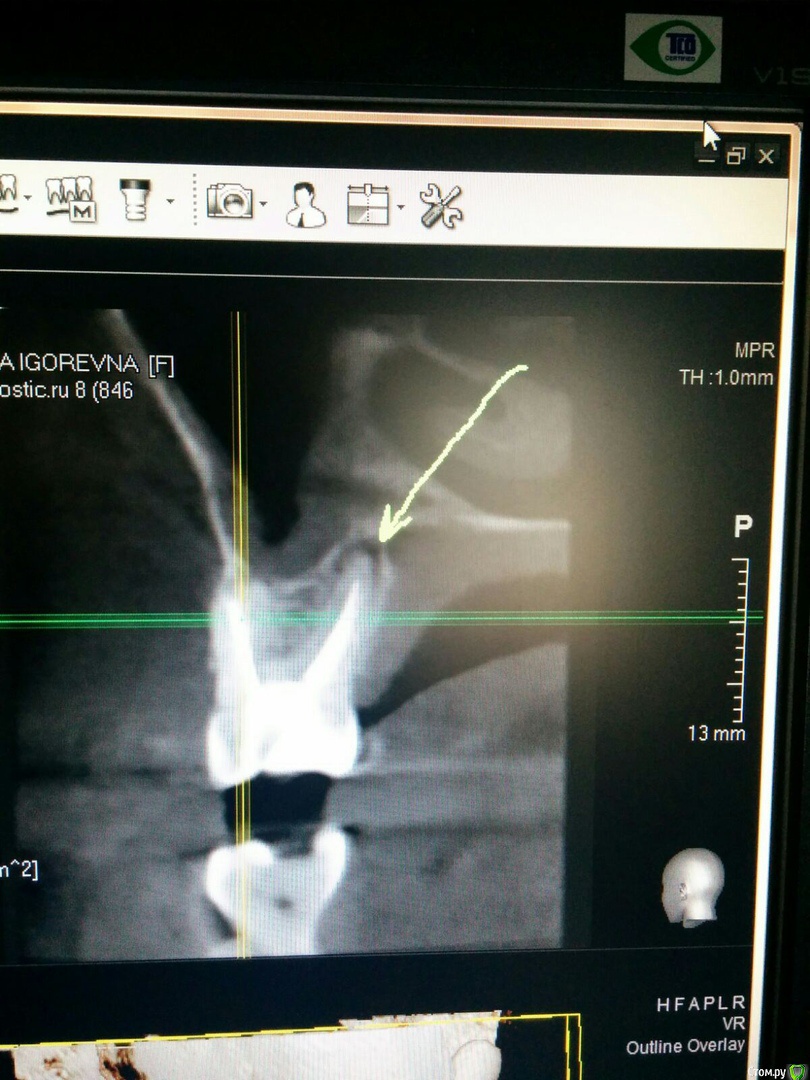

Ксения33 Опубликовано 30 сентября, 2020 Поделиться Опубликовано 30 сентября, 2020 (изменено) Уважаемые доктора, подскажите, пожалуйста, за какой срок восстанавливаются ткани периодонта? Мне перелечивали сложный зуб с хроническим периодонтитом. На снимках были значительные изменения. Как вы считаете, когда целесообразно сделать повторное КТ для оценки состояния периодонта в области этого зуба? Прикладываю снимки до перелечивания каналов. Изменено 30 сентября, 2020 пользователем Ксения33 Ссылка на комментарий